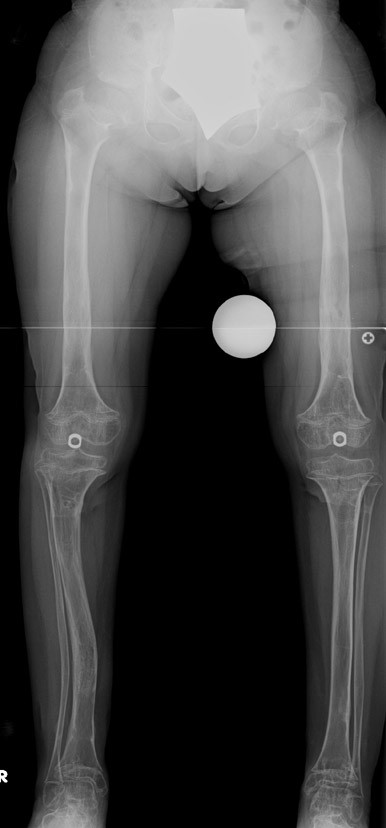

14 ve 16 yaşlar arasında her iki femurda toplam 10-12 cm boy uzatma her iki kalçanın fleksiyon deformitesinin düzeltilmesi (bu lomber hiperlordozu düzeltir) her iki kalçanın varus deformitesini düzeltme ortalama eksternal fiksasyon tedavi süresi = 10-12 ay

12-14 yaşları arasında Her iki tibiada toplam 10-15cm boy uzatma (iki seviyeli uzatma) Proksimal tibianın varus deformitesini proksimal osteotomi ile düzeltilmesi Distal tibianın varus deformitesi distal osteotomi ile düzeltmesi Distal tibianın varus deformitesi distal osteotomi ile düzeltmesi Boy uzatmanın sonunda lateral kollateral ligamentin gerilmesi Ortalama eksternal fiksasyon tedavi süresi = 8-10 ay